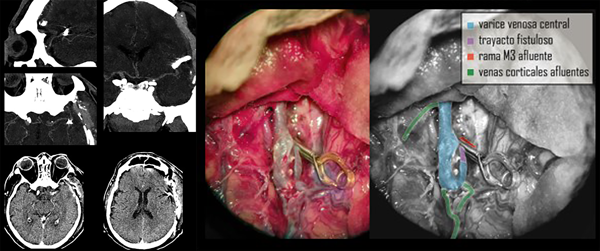

La AngioTC revela craniectomía extensa, retorno a la línea media de estructuras centrales, una nueva área hipodensa que corresponde al territorio vascular de la arteria cerebral posterior izquierda, higroma hemisférico derecho laminar y un hallazgo vascular a nivel del extremo superficial de la cisura silviana, que se observa como un vaso de gran calibre en tiempo venoso del contraste, con un trayecto proximal que termina en contacto con ramas de M3 y un trayecto distal voluminoso que se dirige hacia el polo temporal y se pierde en la base del mismo a nivel del tercio medio de esa misma fosa temporal.

Con los datos obtenidos de este estudio se diagnostica fístula arteriovenosa cerebral, identificando su afluente principal en la cara profunda y superior del trayecto varicoso central, proviniendo aparentemente de ramas de M3 en la profundidad de la cisura silviana. El trayecto varicoso central se extiende sobre la superficie de la cisura homónima y se dirige al polo temporal sin aparente comunicación a los senos durales normales. Se grafican imágenes clave en la Figura 3.

Figura 3. Gráfica de la interpretación de la lesión vascular. En la última imagen de reconstrucción 3D se puede observar la disposición de la várice venosa central que se continúa con un tramo intradural de trayecto sui generis (verde).

Con la premisa de actuar en forma urgente para evitar resangrado y luego de superado un evento infeccioso de origen respiratorio, se decide realizar una nueva cirugía a los 5 días de su ingreso con el objetivo de tratar la lesión vascular de alto flujo. En quirófano se pudieron constatar con precisión los datos obtenidos por imágenes de la angioarquitectura patológica. Se inició por la disección microscópica del valle silviano, exposición de los vasos comprometidos y control proximal vascular de la malformación. Se identificó un trayecto fistuloso de entre 5 y 7 mm de largo que provenía de una rama M3 que drenaba en el trayecto varicoso central. Se realizó clipado transitorio en la base de este trayecto y coagulación de 2 pequeñas aferencias fistulosas a la várice.

Luego de comprobar disminución notable del flujo y el volumen de la várice venosa, se colocó clip definitivo. La várice venosa en su tramo distal presentaba afluentes venosos de caracteres normales que provenían de la corteza, por lo cual no se realizó ningún otro gesto sobre la misma. Se realizó cierre por planos y craneoplastia con polimetil-meta-acrilato (PMMA). Se dejó un catéter subdural para control de la presión intracraneana.

Cuidados neurocríticos postoperatorios

En forma inmediata se tomaron medidas de control de la presión arterial para disminuir los riesgos de sangrado. Al cabo de 24 horas se reinició también la terapia antitrombótica. A las 48h de registro de presión intracraneal normal y sin cambios significativos en el examen físico (paciente sedado en ARM) se realiza imagen de control (TC y AngioTC) en la cual puede observarse ausencia de nuevas lesiones hipodensas, presencia de clip vascular en cisura silviana, permeabilidad de vasos silvianos distales al clipado, disminución significativa del volumen original de la várice venosa, desaparición del higroma contralateral, surcos y cisuras presentes en el hemisferio derecho y ligero edema regional fronto temporal izquierdo (Figura 4).

Figura 4. TC y AngioTC de control postoperatorio y fotografía quirúrgica esquematizada.